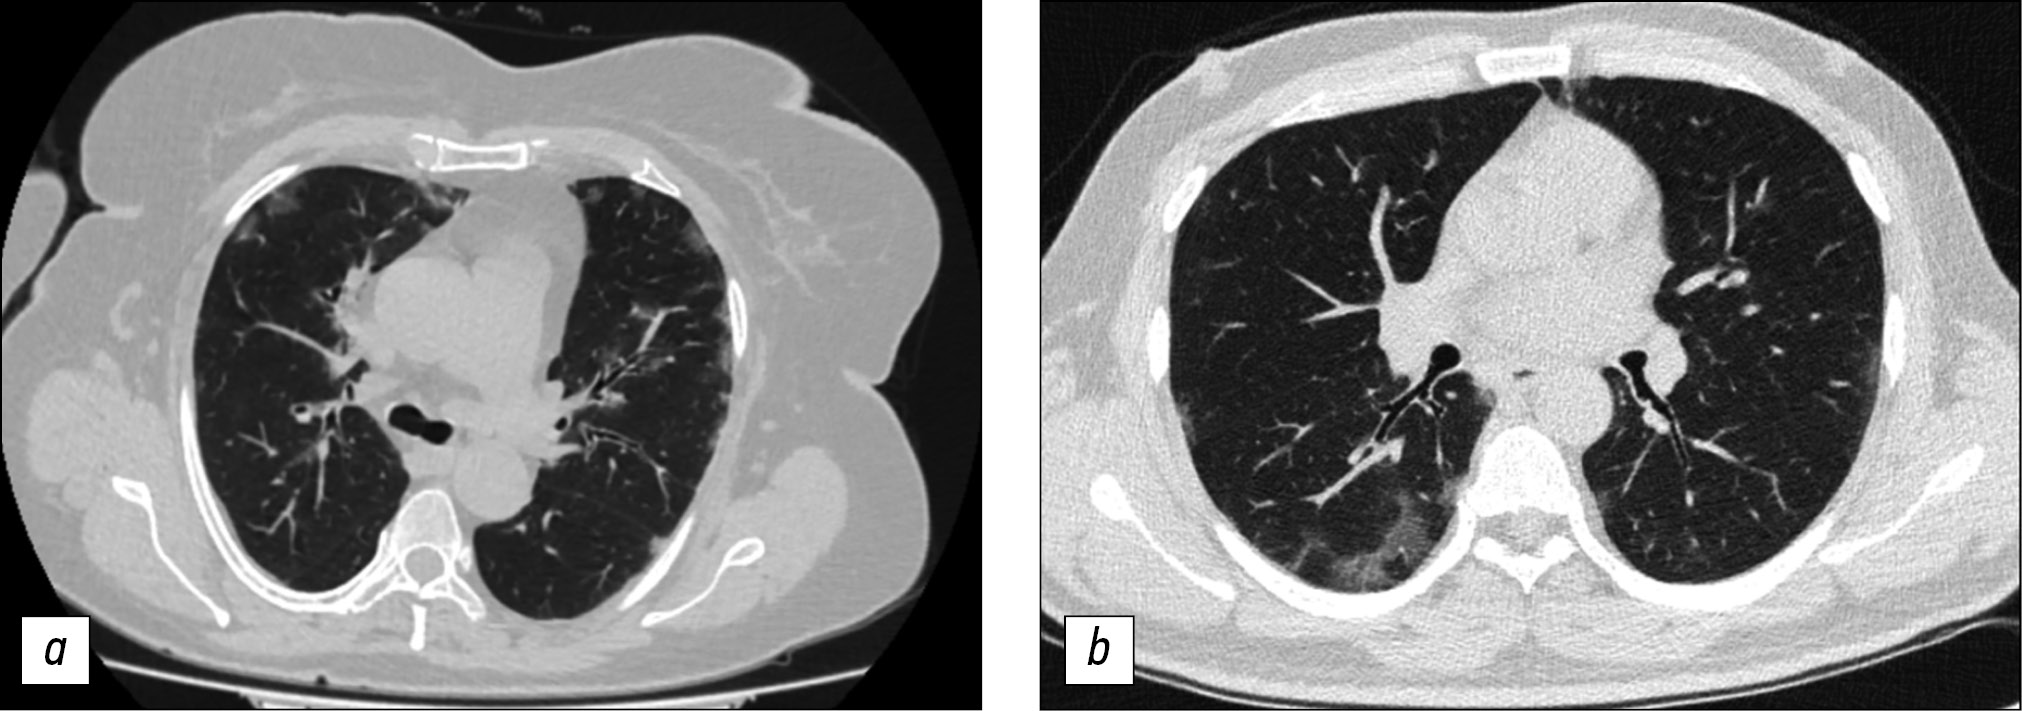

The CT scan of the thoracic organs showed a typical feature of viral pneumonia that is characteristic of the disease, namely extensive bilateral zones or foci of ground-glass opacities with a predominantly peripheral location and the presence or absence of consolidation zones, in all the 65 patients with COVID-19.

With the development of severe infectious diseases, SARS abnormalities of the lung parenchyma eventually spread to the central region and upper lobes of both sides [11, 12]. In our study, the progression of COVID-19 on CT images (13.8%) confirmed these findings (Fig. 2).

In the group of patients with COVID-19, the disease was predominantly peripheral (subpleural) and was noted in the middle and lower lung fields on the initial CT scan of the thoracic organs. Further studies revealed that pulmonary consolidation and fusion of infiltrates extended into the upper lobes of the organ as the disease progressed and affected them, as all five lobes of both lungs were affected in some patients, while “white” lungs were seen on CT. In our study group, an increase in the number of cases of ground-glass opacity and consolidation density indicated the progression of the disease, while the emergence of fibrosis and the resolution of the areas of ground-glass opacity or consolidation indicated improvement. However, the deformation of the bronchus due to fibrosis can lead to irreversible changes and affect the patient’s respiratory function. These data suggest that lung lesions in COVID-19 may be present before the patients become symptomatic, and that CT should be performed promptly, even if the disease is asymptomatic.